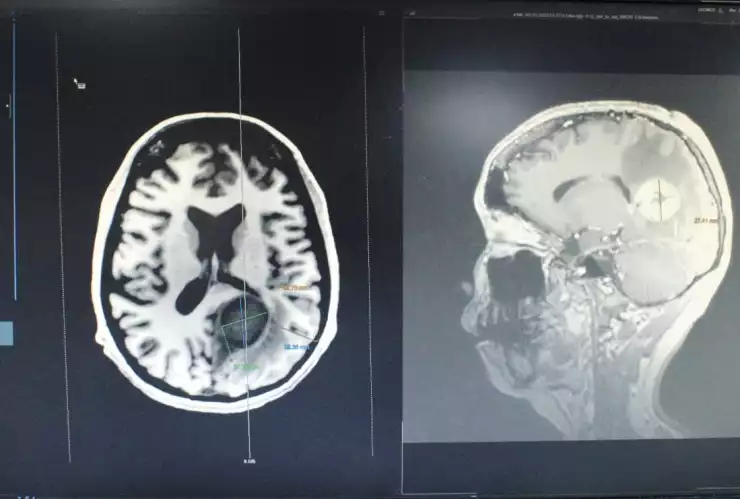

Ante este descubrimiento se le realizó una tomografía donde se observó una lesión dentro del cerebro.

En estudio de resonancia magnética identificamos una lesión nodular con bordes bien definidos y con gran edema cerebral

En la neurocirugía practicada a la mujer es un procedimiento de alta especialidad en el que se utiliza tecnologías médicas como microscopio quirúrgico, neuronavegador y ultrasonido transquirúrgico, con el propósito de realizar un acceso hacia el tumor localizado en la parte profunda del cerebro.